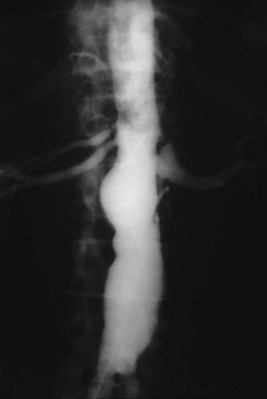

In general, atherosclerosis affects patients in the sixth to seventh decades of life. The diagnosis of renovascular hypertension caused by atherosclerosis is being discovered in younger patients, which may be attributable to increased imaging studies. Atherosclerosis may be limited to the renal artery in 15% to 25% of patients but tends to be part of a generalized process affecting the major arterial branches of the aorta. Bilateral disease is present in up to 40% of patients (Fig. 54–41). Unilateral disease is more common in the left renal artery with contralateral disease present in 40% at the 4-year mark (Libertino et al, 1988). Although renal arteries are end arteries by anatomic definition, the slow onset of atherosclerosis permits development of collateral vessels, resulting in minimal clinical symptoms.

Primary intimal fibroplasia accounts for 10% of lesions and occurs in children and young adults. The process can develop in contralateral kidneys or other vessels in a progressive nature. Angiographically the disease has smooth, focal stenosis involving the proximal or middle portion of renal vessels or branches (Fig. 54–42).

Medial fibroplasia accounts for 75% to 80% of fibrous lesions primarily in women between 25 and 50 years of age. With angiography, arteries demonstrate a “string of beads” in the distal two thirds of the main renal artery and its branches (Fig. 54–43). Multiple microaneurysms can also be appreciated. An estimated 33% demonstrate progression, whereas complete occlusion is rare.

Figure 54–43 Selective right renal angiogram demonstrating medial fibroplasia “beads on a string” in a solitary right kidney.

Perimedial (subadventitial) fibroplasia accounts for 10% to 15% of fibrous lesions and is limited to the renal arteries. Angiographically the appearance is similar to that of medial fibroplasia but there are no microaneurysms and extensive collateral circulation is present (Fig. 54–44). Without intervention this entity leads to severe stenosis and progressive obstruction with ischemic nephropathy. The disease often afflicts young females.

Figure 54–44 Selective right renal angiogram demonstrating perimedial (subadventitial) fibroplasia with decent collateral vasculature.